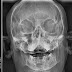

Fratura do Complexo Zigomático-Orbitário (novembro/2018)

Paciente 58 anos, vítima de acidente com bicicleta elétrica, apresentando fratura do complexo zigomático esquerdo (sutura fronto-zigomática ...

Fratura de Sínfise Mandibular 2 (outubro/2018)

Paciente 42 anos, vítima de queda da própria altura, apresentando fratura completa de parassinfise mandibular e fratura incompleta e sem des...

Fratura de Sínfise Mandibular 1 (outubro/2018)

Paciente 27 anos, vítima de acidente motociclístico, apresentando fratura de parasinfise mandibular esquerda recente. Desalinhamento entr...